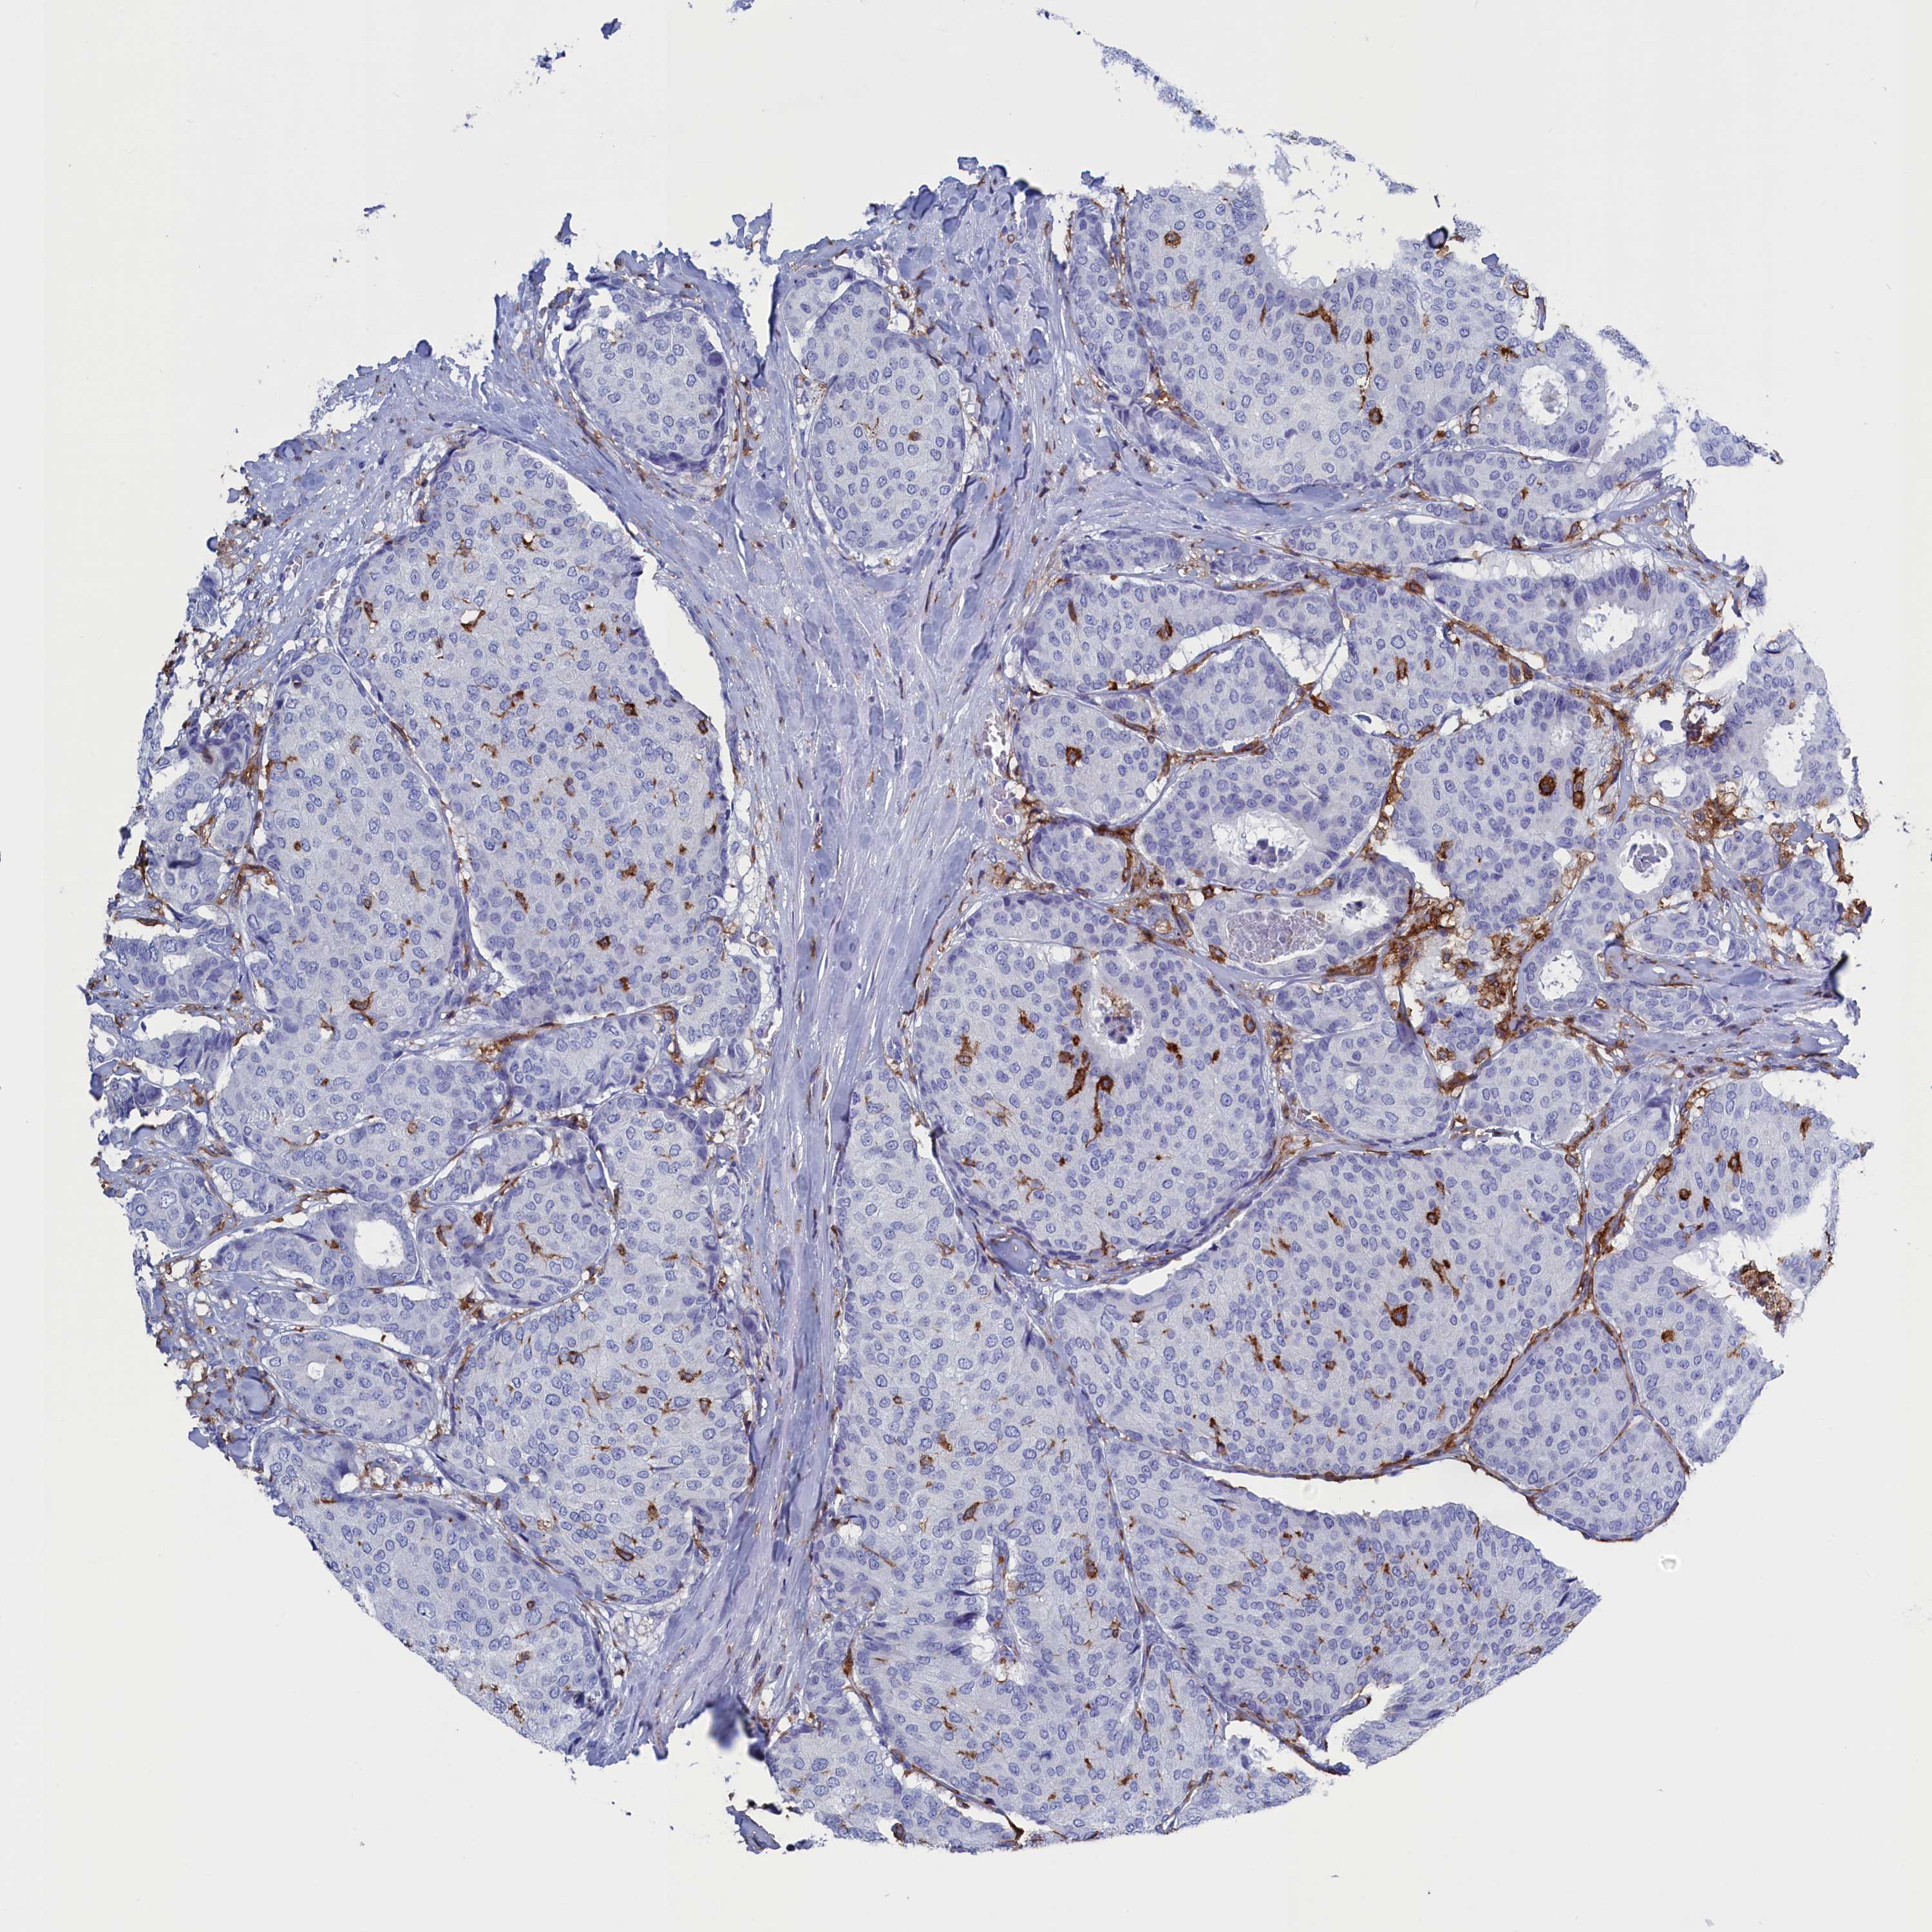

BRCA TCGA BRCA VALIDATION PROTEIN EXPRESSION